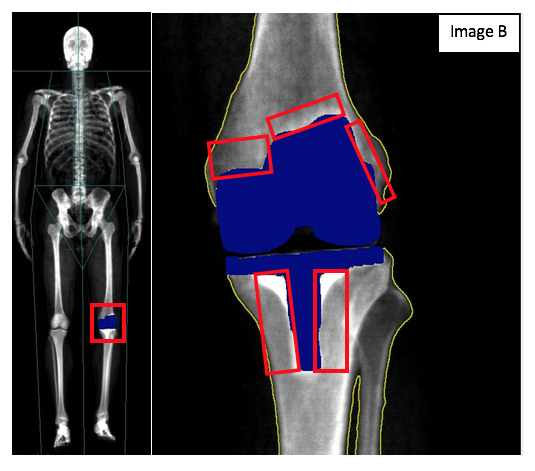

A few weeks after a successful surgery, I was able to repeat the two DXA scans in this individual (Image B). I repeated both the total body scan as well as the isolated left knee taken after knee replacement surgery. On the total skeletal view, you can easily see the knee replacement on the left knee as the blue object (highlighted by a red box). If you look at the isolated scan of the left knee again, you get an excellent view of the knee replacement. Looking at the femur you can clearly see the cap that is placed around the tibia and you can see the base of the knee replacement that is placed into the tibia. While not appropriate to diagnose whether a knee replacement surgery is necessary, DXA may actually be valuable when examining the knee replacement over time. Most knee replacements used today are thought to have a lifespan of 20-30 years (WebMD, 2019). Therefore, most individuals will not have to worry about having to have a second replacement if they have had their knee replacement done late in their life. The DXA scan may be useful in these individuals to check on the bone around the actual replacement itself. Since some knee replacement surgeries use an acrylic cement to bond the replacement parts to the bone of the knee joint there is a possibility of bone loss at these contact points. If you look at the isolated post-surgery image, you can see those areas of contact between the knee replacement and the bone where the acrylic cement has been used to bond the bone and the knee replacement. By examining these areas and looking at the bone mineral content (BMC) as well as the bone mineral density (BMD) it is possible to monitor these areas for increased bone loss due to the acrylic cement.

Two things stick out for me regarding the DXA scans below. The first is that, even though it is not used to diagnose whether a knee replacement is appropriate, the DXA scan was, in fact, able to pick up the damage that made a knee replacement necessary. The second is the potential to use the DXA to monitor the health of the bone surrounding the knee replacement. Over time, subsequent scans of this individual and others like him will be useful in determining the benefits of DXA technology in monitoring long-term recovery as it relates to bone health.